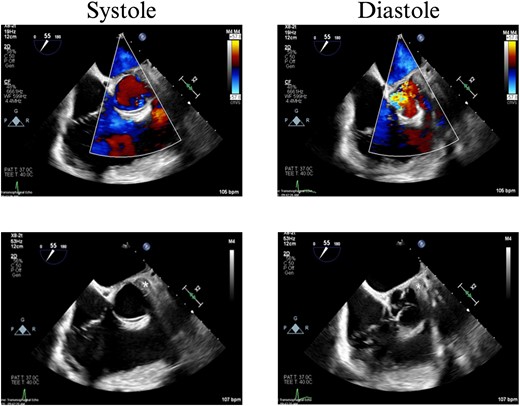

In the OR, exploratory laparotomy, right nephrectomy, liver packing, and pericardial window were performed. The pericardial window was negative for blood. With no suspected cardiac injury, intraoperative fluoroscopy (Fig. 1) and transesophageal echocardiogram (TEE) (Fig. 2) were used to locate the bullet. It was suspected to be intravascular secondary to venous embolism from the retro-hepatic inferior vena cava (IVC). Cardiothoracic surgery was consulted for removal of the bullet. With abdominal hemorrhage controlled, the surgeons agreed the patient was an acceptable risk for anticoagulation and cardiopulmonary bypass. Sternotomy was performed, the patient was placed on cardiopulmonary bypass, and the bullet was removed through a right atriotomy.

Intraoperative TEE demonstrating the intravascular bullet in the IVC.

Case 1 involved a stable patient with a single GSW to the left back and a retained bullet over the right ventricle. The trauma team identified the bullet overlying the cardiac silhouette and performed a CT scan to determine its trajectory. The scatter artifact complicated localization, but a pericardial window excluded cardiac injury. Intraoperative imaging (fluoroscopy and TEE) revealed a venous bullet embolism from the retro-hepatic IVC to the right ventricle. The bullet was mobile on fluoroscopy, and TEE provided the best imaging. The trauma and cardiothoracic surgeons discussed bullet removal timing, considering the patient’s stability and heparinization needs. They opted for immediate removal due to the potential lethality of pulmonary artery embolism. The operation was successful, requiring only one surgery for definitive management. This case highlights the success of immediate bullet removal in hemodynamically stable, asymptomatic patients with venous embolism.